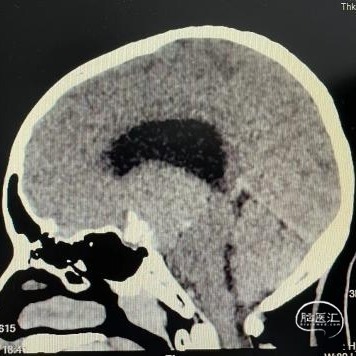

头部CT平扫显示:全鞍型蝶窦,鞍区-鞍上区-第三脑室可见一混杂密度肿块,内可见多发钙化灶,最大层面大小约43mm*35mm(左右径-前后径),CT值30HU,双侧脑室明显扩张,室旁可见对称性条片状低密度灶。